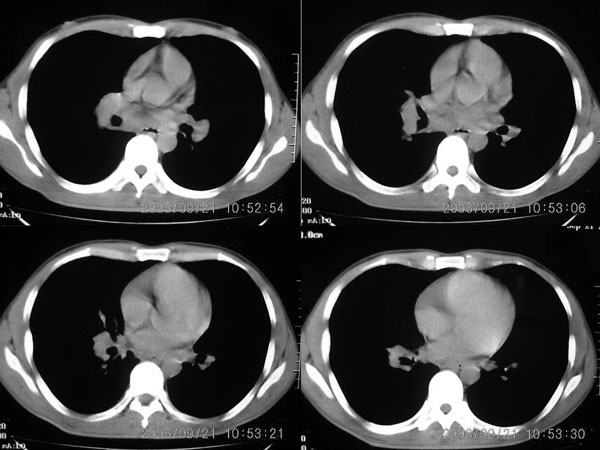

两肺弥漫均匀分部粟粒壮影 右肺基底段不规则软组织密度影其内密度不均 纵隔内淋巴结钟大 请进一步右肺病灶薄层检查及补充病史后再会诊

两肺弥漫均匀分部粟粒壮影 右肺基底段不规则软组织密度影其内密度不均 纵隔内淋巴结肿大,考虑间质性炎变。不除外职业病改变

右肺下叶后基底段结节样病灶,边界不规则,密度不均,右肺门团片影,肺门增大,纵隔见肿大淋巴结.考虑纵隔及肺部淋巴瘤.建议传上纵隔片.

两肺粟栗样病灶,右肺门及纵隔淋巴结增大,考虑结节病!须进一步检查免疫系统。

右下肺脊柱旁结节样肿块,可见毛刺,右侧肺门影增大,并见气管隆突前、主动脉窗内多发结节影。

临床无明显发热,男 27岁 咳嗽一个月,治疗无效。

考虑青年人周围型肺癌并右肺门、纵隔淋巴结转移。